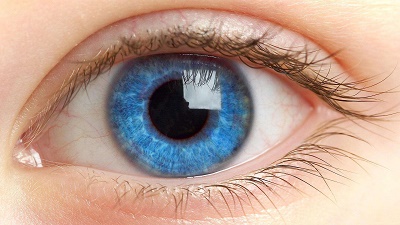

قیمت: 39٬000 تومان - دسته بندی فایل: مباحث رشته هاتعيين تغييرات حساسيت کانتراست با افزايش سن

بررسی حساسیت کانتراست با افزایش سن در بیماران مراجعه کننده به کلینیک بینائی سنجی دانشگاه علوم پزشکی مشهد